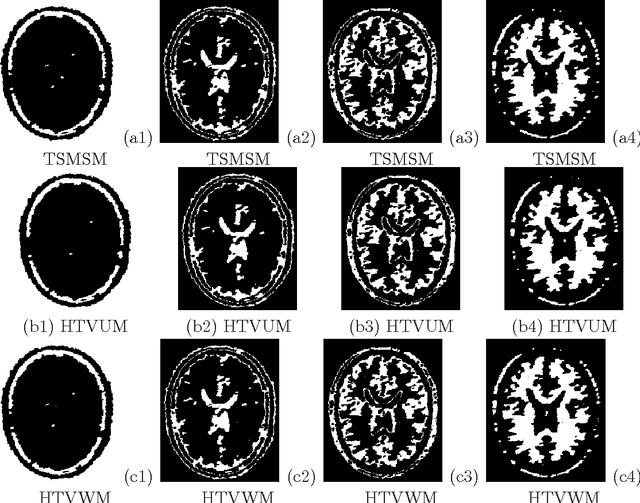

Abstract:The performance of image segmentation highly relies on the original inputting image. When the image is contaminated by some noises or blurs, we can not obtain the efficient segmentation result by using direct segmentation methods. In order to efficiently segment the contaminated image, this paper proposes a two step method based on the hybrid total variation model with a box constraint and the K-means clustering method. In the first step, the hybrid model is based on the weighted convex combination between the total variation functional and the high-order total variation as the regularization term to obtain the original clustering data. In order to deal with non-smooth regularization term, we solve this model by employing the alternating split Bregman method. Then, in the second step, the segmentation can be obtained by thresholding this clustering data into different phases, where the thresholds can be given by using the K-means clustering method. Numerical comparisons show that our proposed model can provide more efficient segmentation results dealing with the noise image and blurring image.